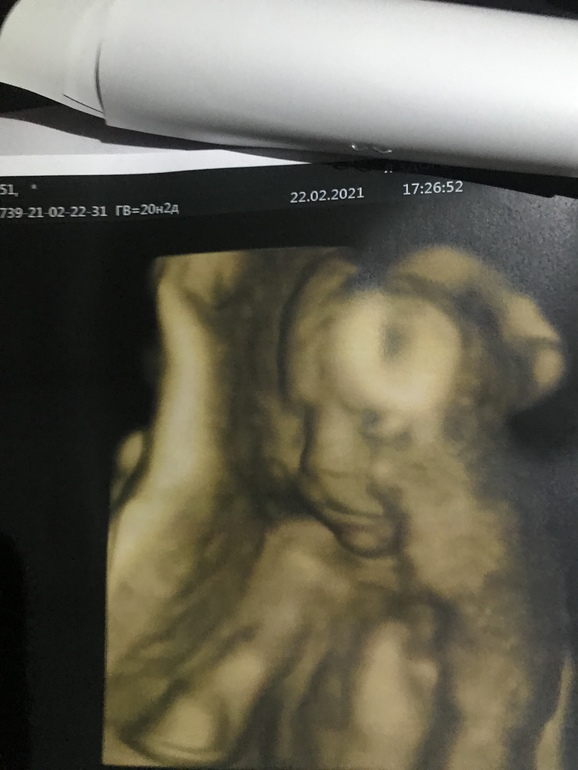

Сыночек +- на 384 грамма, идёт по сроку с небольшим опережением. В сердечке нашли хорду один в один таких же размеров и такого же расположения, как была у Аарона. Не критично, да и надеюсь что как и в случае со старшеньким, рассосётся к родам. На всех фотографиях тоже видно сходство с братом уже сейчас: выпяченная вперёд верхняя губа выдаёт))

Вот он, малышочек: